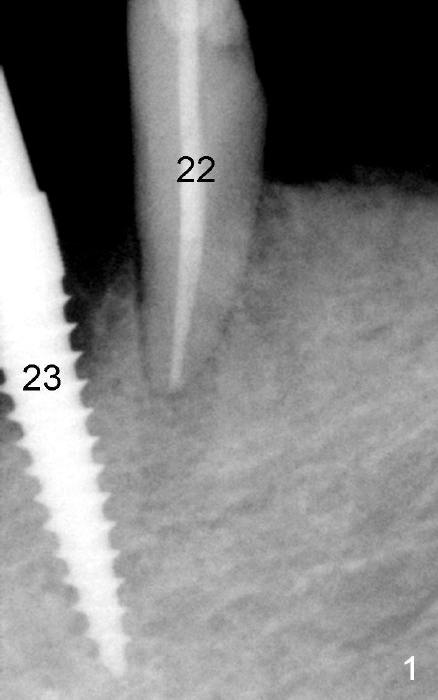

The tooth #28 has also been exfoliated for a few days. A 4.5x17 mm two piece implant is placed (Fig.4, as compared to Fig.3 preop) and immediately loaded (Fig.5, taken 6 days postop).